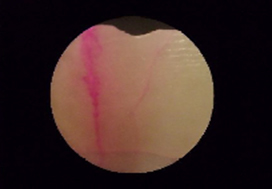

治療前:赤い部分は歯が溶けている部分

治療後:赤い部分が消えて歯が強化された